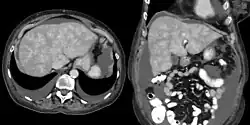

CT appearance of liver in congestive hepatopathy, sometimes referred to as a nutmeg liver. Due to congestion, contrast does not flow through the liver in a normal manner. Axial and coronal images in the portal venous phase.

Increased pressure in the sublobular branches of the hepatic veins causes an engorgement of venous blood, and is most frequently due to chronic cardiac lesions, especially those affecting the right heart (e.g., right-sided heart failure), the blood being dammed back in the inferior vena cava and hepatic veins. Central regions of the hepatic lobules are red–brown and stand out against the non-congested, tan-coloured liver. Centrilobular necrosis occurs.[2]